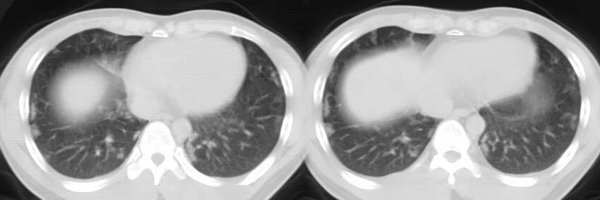

以下是引用ssl1_1在2006-3-2 22:37:00的发言:[br]肺泡蛋白沉积症(外围型)

以下是引用huangaiying1在2006-3-3 16:03:00的发言:[br]双肺弥漫分布的磨玻璃影及小结节影,以双上肺为著,纵隔内未见明显增大的淋巴结影,结合病史,考虑过敏性肺炎

以下是引用guandong在2006-3-4 20:57:00的发言:[br]两肺弥漫分布磨玻璃影,以中外带为主,可见于过敏性肺炎、肺泡蛋白沉着症、农民肺等,但不支持结核。